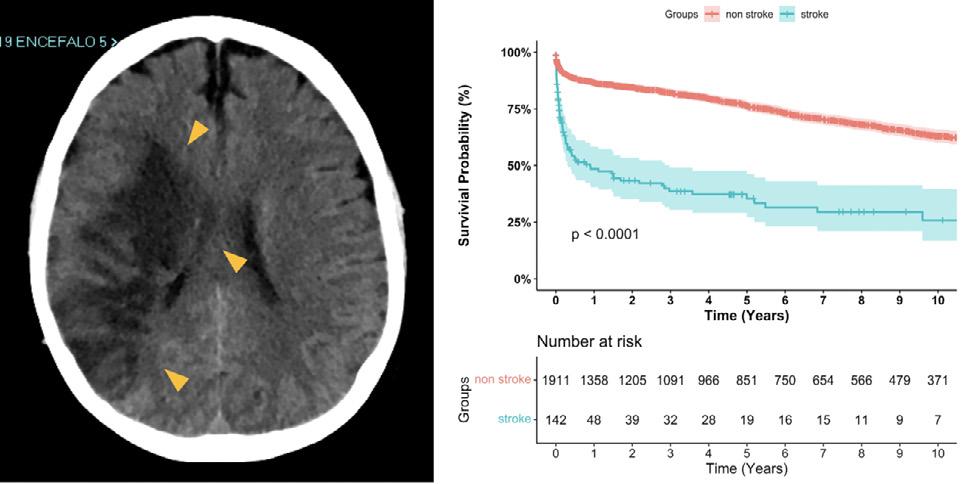

Stroke after aortic arch surgery: results and risk factors from 2095 patients

G. Murana, Bologna, D. Levine, New York, NY, T. Hiroo, New York, P. A. Kurlansky, New York, Y. Ning, New York, A. Costantino, Bologna, L. Di Marco, Bologna, D. Pacini, Bologna. Giacomo Murana 1 MD, PhD

1 Division of Cardiac Surgery, IRCCS, Azienda Ospedaliero-Universitaria di Bologna, Alma Mater Studiorum – University of Bologna, Italy.

Despite the development of effective cerebral protection techniques, stroke is a major complication of aortic arch surgery, with a multi-centric analysis reporting a 5.7% and 3.3% incidence of focal permanent or transient neurological defects respectively1.

Open questions are that cerebral protection strategies are still vastly heterogenous among centres and endovascular techniques are gaining much popularity on proximal arch pathologies.

Our study aims to better understand the preoperative and intraoperative factors linked to stroke. It includes an exceptionally vast casuistry, combining the experience of two aortic centres: Bologna Alma Mater Studiorum (ITA) and the Columbia University (US). Population was 2095 patients who underwent aortic arch surgery over a 20-year-span, from 2000 to 2021.

The only preoperative characteristics significantly linked to post-operative stroke were diabetes, age and acute type-A dissection.

More surprisingly, stroke wasn’t associated with the site of arterial cannulation if antegrade cerebral perfusion was assured, but only to longer cardio-pulmonary bypass time and lower temperatures (DHCA vs ACP OR 2.79). Also, the extent of arch replacement, including the trunk procedure, wasn’t a risk factor and the addition of aortic root replacement was linked to lower stroke rates.

Stroke proved to be crucial, influencing both the short-term prognosis of the patients, associated with renal and respiratory failure, longer hospital stays and higher in-hospital mortality, as well as long-term prognosis. During our follow up, stroke was linked to lower one, five and ten-year survival with a 3.17 hazard ratio for late death.

As our data points out, the extension of the surgery both with ET and FET and aortic root substitution doesn’t lead to higher incidence of stroke given effective cerebral protection is achieved, therefore it should always be practiced when indicated.

On the contrary, two main factors play a central role: patient selection and antegrade cerebral perfusion. First, oculate patient selection is key for clinical success, as highlighted by the most recent guidelines on aortic arch treatment 2 , which denounced the lack of specific clinical prediction models. Second, moderate hypothermia and selective cerebral perfusion proved to be superior to deep hypothermic circulatory arrest in preventing stroke and confirmed themselves to be the gold-

Giacomo Murana / Division of Cardiac Surgery, IRCCS, Azienda OspedalieroUniversitaria di Bologna, Alma Mater Studiorum - University of Bologna, ItalyFigure 1: Survival probability of post-operative stroke after aortic arch surgery